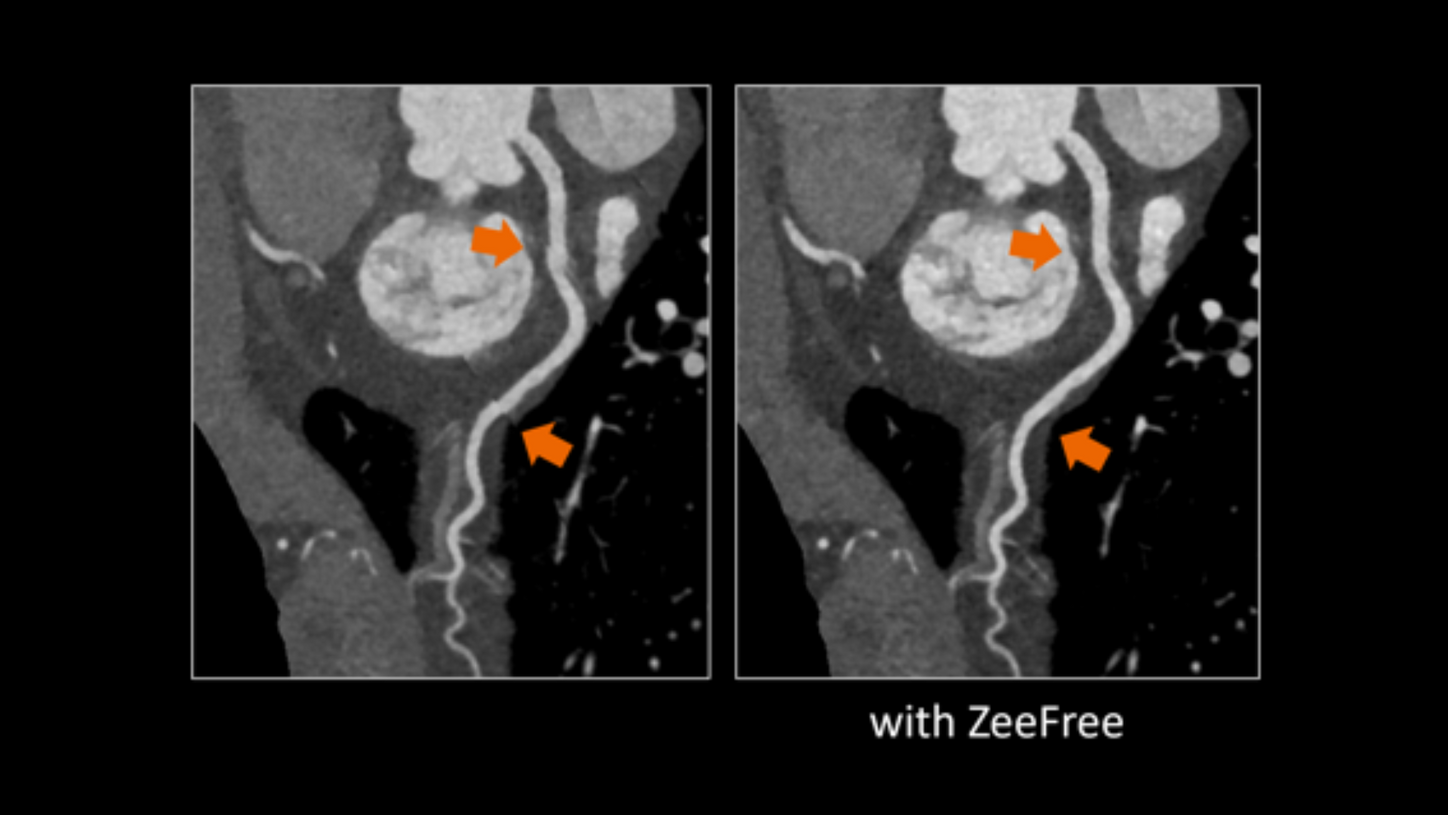

ZeeFree

A novel reconstruction feature that enables optimal cardiac imaging independent of the detector width. It reduces misalignments usually originating from patient movement, breathing or adjacent cardiac cycles.

Optimal Cardiac CT imaging with ZeeFree

With ZeeFree, a novel cardiac CT reconstruction feature employing intelligent algorithms to automatically align image stacks, you get images that are optimally aligned to display the morphology as intended, without misalignment of stacks. Zeefree operates on a detector width-independent algorithm, and is adaptable to both retrospective ECG-gated spiral and prospective ECG-triggered sequence acquisitions. Learn more in the white paper.